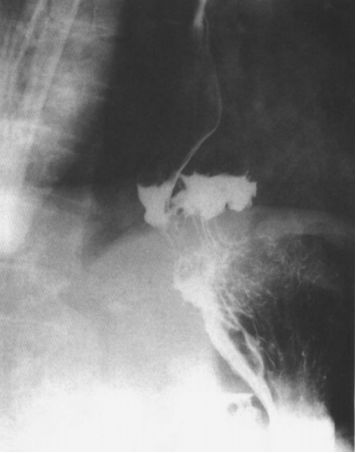

食管癌

因为食管癌的造影很复杂,所以不能用一句话简单概括。下面按照食管癌的早期和中晚期分别总结。

早期:局限 小(局限性黏膜皱襞紊乱和断、局限性管壁僵直;小充盈缺损、小龛影。)

中晚期:无“局限 小”(中晚期食管癌是整个食管的改变,不再是局限性改变。管壁僵直;充盈缺损、龛影;管壁狭窄。)

早期中下段食管癌

食管中下段黏膜皱襞局限增粗,中断,箭头所示,管壁僵硬。

早期食管癌

中晚期食管癌图像: